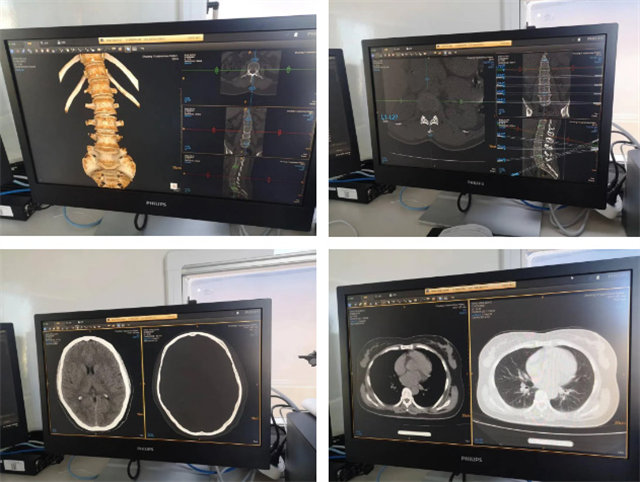

提升医疗服务质量,医院改善体检就医体验。移动CT体检车投入使用,采用了移动CT高端设备,精准体检检查,移动服务。这个相当是个移动的CT检查室。可以开到需要的地方进行CT检查,大大缓解医院压力,特别是可以解决检查人数多,等待时间长的问题。移动机动性可以深入到各个地方,开展义诊,科普,检查等医疗检查服务。让大家在附近就可以享受到高端的CT检查。

检测范围比较广泛,可以全身扫描检查。头部、颈部、胸部、四肢、关节等。三维成像,低剂量儿童患者成像;常规胸部体检CT检查和肺癌早期筛查。孕妇跟准备怀孕的女士不适宜参加CT检查,因为辐射会对胎儿有影响。婴幼儿需要做好防护,避免CT检查伤害到其他器官,不要穿戴金属首饰。检查扫描过程需要保持冷静。不要乱动才能保障图像检查的清晰度和没有重影。